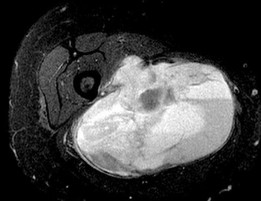

A 15-year-old male presents with deep knee pain awakening him at night. Radiographs show a permeative destructive lesion in the distal femoral metaphysis with a 'sunburst' periosteal reaction and Codman's triangle.

Biopsy confirms high-grade conventional osteosarcoma. What is the most critical prognostic factor for long-term overall survival in this patient?

Explanation

For localized high-grade osteosarcoma, the most important prognostic indicator is the histologic response to neoadjuvant chemotherapy. This is evaluated during the definitive resection. A 'good response' is typically defined as greater than 90% or 99% tumor necrosis. Patients who achieve this level of necrosis have a significantly improved disease-free and overall survival rate compared to 'poor responders' who have extensive viable tumor cells remaining.